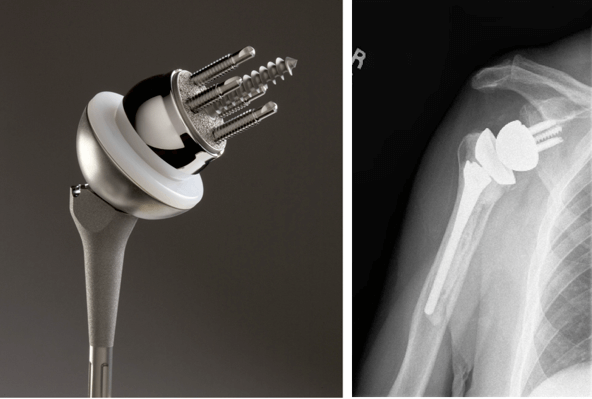

• Обратная артропластика плечевого сустава: импланты замещают суставную впадину лопатки и головку плечевой кости, но меняется нормальное соотношение деталей шаровидного сустава:

о Используется у пациентов с необратимым поражением ротаторной манжеты плеча и вторичной артропатией, болевым синдромом и псевдопараличом (невозможность поднять руку больше, чем на 90°)

о Если поменять местами суставную впадину лопатки и головку плечевой кости, меняется центр вращения:

- Рука расположена ниже (удлинение) и медиальнее: смещается центр вращения дистально и медиально:

Приводит к повышению управления плечевого сустава дельтовидной мышцей

о Четыре главных компонента: ножка протеза, полиэтиленовая чаша, гленосфера (шар) и метаглен (основа для суставной впадины лопатки):

- Ножка протеза плечевой кости: металлическая, с цементной или бесцементной фиксацией, с чашеобразной проксимальной частью

- Полиэтиленовая чаша: соответствует проксимальной части плечевого компонента протеза, углубляя чашу

- Гленосфера: металлический шар, присоединенный к метаглену

- Метаглен: металлическое основание с плоским креплением к поверхности гленоида, закрепленной спонгиозными винтами

о Используется при необратимом поражении ротаторной манжеты плеча и вторичной артропатии, болевом синдроме и псевдопараличе (невозможность поднять руку больше, чем на 90°)

о Если поменять местами суставную впадину лопатки и головку плечевой кости, меняется центр вращения; это приводит к повышению управляемости плечевого сустава дельтовидной мышцей, особенно передней и задней ее частями